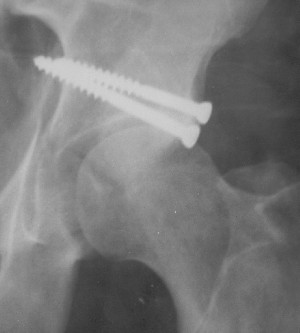

19/05/03

Послеоперационный снимок прямой 5/05/03

|

Послеоперационный снимок боковой 5/06/03

Больной 18 мая 2003 года в автоаварии получил перелом левой вертлужной впадины, вывих бедра. Госпитализирован в один из стационаров области.Вывих вправлен. В последствии бедро вывихивалось еще дважды. На консультацию был представлен снимок от 19.05.03г., больной переведен к нам 3.06.03г. Снимок при поступлении - перелом впадины, задне-верхний вывих бедра. 05.06.2003 г. выполнено открытое вправление вывиха левого бедра и остеосинтез стенки вертлужной впадины двумя винтами. Послеоперационный период без осложнений. Объем движений в левом тазобедренном суставе восстановился полностью. Выписан на амбулаторное лечение в удовлетворительном состоянии с рекомендациями 3 месяца ходить на костылях без нагрузки на оперированную конечность. На контрольных рентгенограммах левого тазобедренного сустава 13.10.2003 г. - признаки консолидации перелома; плотность, форма головки и состояние суставных поверхностей удовлетворительные. Разрешена дозированная осевая нагрузка, на конечность с использованием дополнительной опоры. 19.12.2003 г. больной обратился с жалобами на боли в левом тазобедренном суставе. На рентгенограммах левого тазобедренного сустава 19.12.2003 г., 20.02.04г. - асептичекий некроз головки бедра. 5.04.04г. - эндопротез. Сейчас ходит без трости, не хромает. Особенность эндопротезирования - при удалении винтов прослежена линия перелома заднего края впадины и предложено установить чашку несколько меньшего диаметра, чтобы она была покрыта несломанной частью.